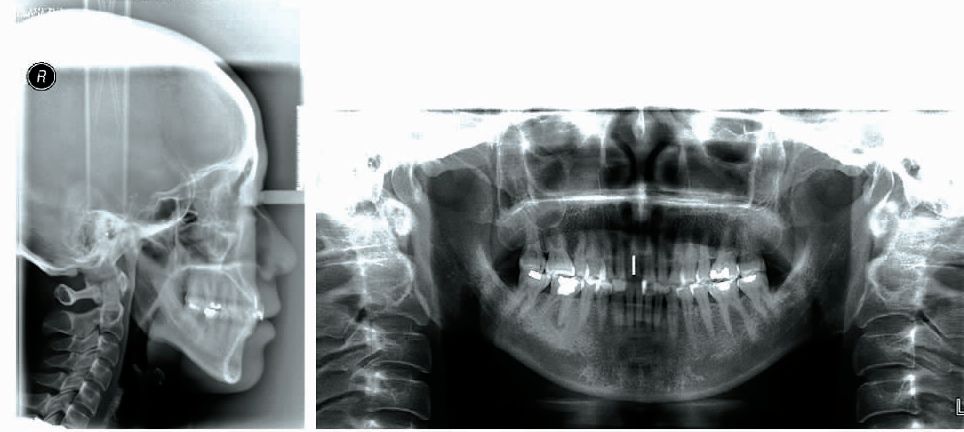

正面观 :卵圆形脸,面部左右基本对称。 侧面观: 直面型,下颌平面角高。 牙列情况: 恒牙(牙合),双侧磨牙及尖牙均为中性关 系,前牙深覆(牙合)Ⅱ度,覆盖2mm,右上中切牙残根, 下牙列轻度拥挤,双侧下颌磨牙大面积充填体(图1)。双侧颞下颌关节检查:开口度正常,开口型正, 双侧颞下颌关节区域无压痛,张闭口时未触及关节弹响及杂音。

X线检查

治疗前曲面断层片:右上中切牙残根。右下第一磨牙大面积高密度充填体及髓,未见根充影像,近中根尖低密度影环绕。头影测量见表1。